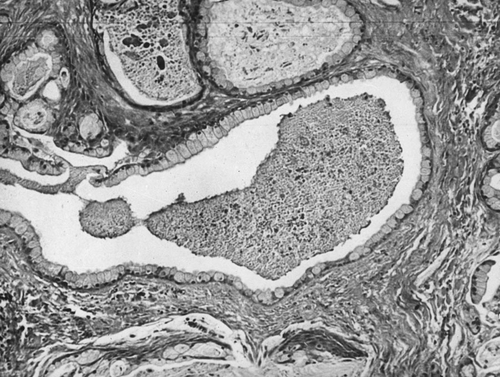

● Низкозлокачественный. Многочисленные макро- и микрокистозные полости, выстланные слизистыми клетками, мелкоочаговый гиалиноз стромы (рис. 12-3).

Рис. 12-3. Низкозлокачественный мукоэпидермоидный рак слюнной железы. Окраска гематоксилином и эозином (x120).